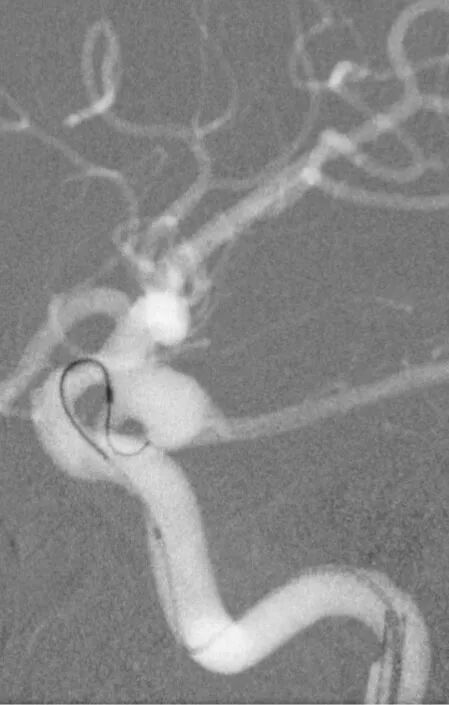

释放支架

找到支架与弹簧圈之间的切线位,继续填塞。支架很好地保护住了颈内动脉和后交通动脉

最后的填塞结果